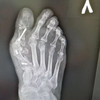

Хочу написать отзыв о враче Чернышове Н. А. который является так же директором центра как и «хирургом»..... 5.11.2025 была прооперирована (Удаление вальгусной диформации) мама у этого доктора если так можно назвать. Вроде бы все нормально поначалу как казалось, 21.11 2025 сняли швы и тут доктор начал говорить намёками что операции приходится повторять и тд… 26. 11.25 вынал спицы врач Пасечник, после этого пальцы второй третий стали кривыми как изначально и боль была в течении 3х дней. 22.12.25 с новыми снимками приехали к врачу с новыми снимками, я выразила свое недовольство что если на правой ноге более менее результат есть то на левой его нет совсем, на левой ноге не заживает глубокая рана, нога опухшая, на что он сказал нужно переоперироваться, опять оплатить якобы за расходные материалы....А так все нормально у вас. На что я сказала почему мы должны платить если с первого раза вы результат не сделали… Ответа не было… Шли дни из ноги началась выделяться жидкость, затем гной, 30.12.25 около 21 часа я наконец то дозвонилась Чернышове Н. А. отправила фото ноги с гноем, он сказал срочно ехать в Семилуки в больницу ложится, так как НМЦ закрыт на праздники… В суете и переживаниях собрались поехали в метель в Семилуки, хотя странно почему в Семилуки, потом понятно стало там зав. отделения Чернышов М. А???? Не право ли совпадение… Маму положили, назначили антибиотики, сожгли ногу Бетодином ежедневно уливая им её. Взяли анализы, это тоже история превышен белок у неё, а ей об этом никто ни слово и не обследовали… Выписали, поехали мы в НМЦ к ЧЕРНЫШОВУ Н. А. Он обработал хлоргексидином и все, нога опухшая, рана открыта, на вопрос может кроме хрлгексидина нужно купить что то ещё он со злостью ответил не надо тут самолечением заниматься. А нужно было почистить рану вынуть белое скопление которое не давало стягиваться и заживает, не говоря о том что отломок кости после операции остался не тронутым!!! По анализам перед операцией был восполительный процесс, оперировать нельзя было, но как же день назначен терять центру 261000 не хотелось бы.... Итог на данный момент мама ходит в спец. обуви, рана ещё не затянулась, из дома естественно она не выходит 4 месяца как. Врач после всего естественно общается с недовольством, пишите притензию в юр. отдел наш написал в личные сообщение… Рассказала вам нашу историю, надеюсь может кому то поможет что надо обходить этот центр и этого хирурга далёкой стороной, хотя на сайтах одни положительные отзывы, которому важно только заработок, а не здоровье и восстановление пациента.